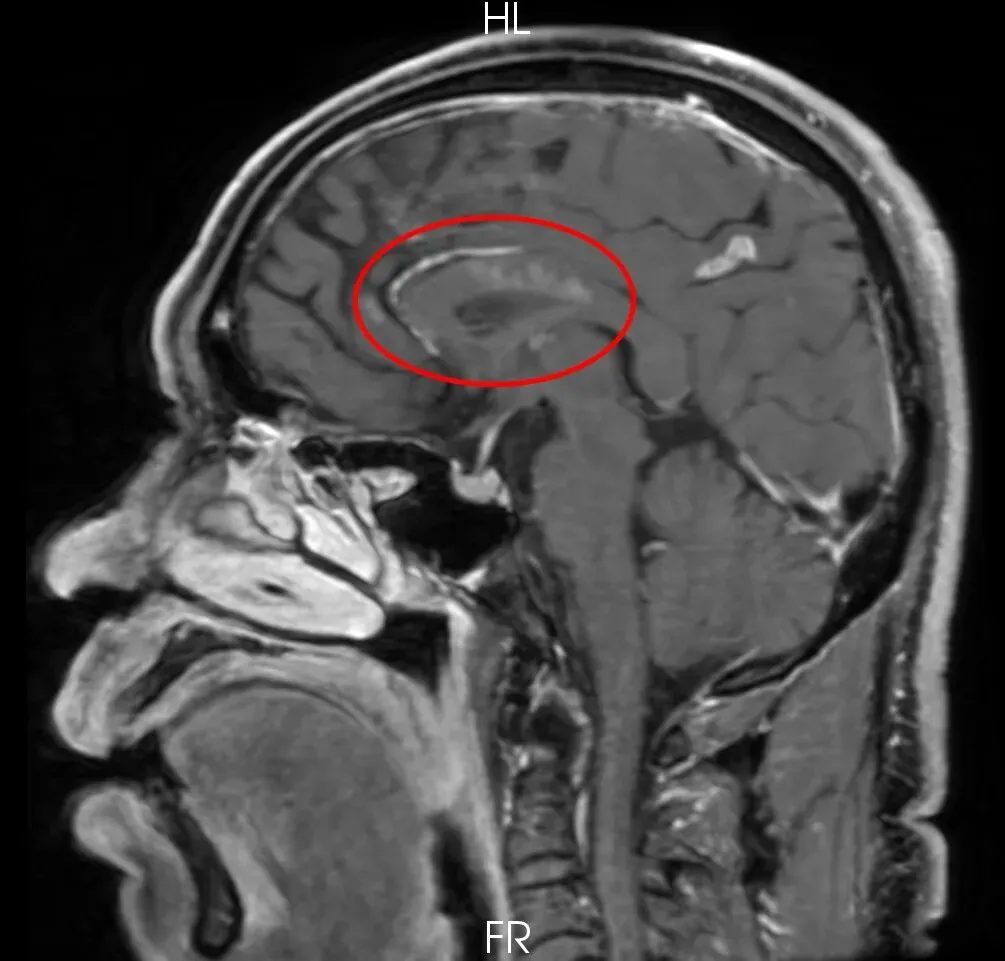

检查结果清晰显示,患者脑血管管壁存在多发环周增厚,右侧大脑前动脉闭塞且伴有管壁广泛强化,结合临床症状与影像特征,医学影像科团队初步判断患者罹患“中枢神经系统血管炎”。这一疾病属于少见且复杂的病症,病因尚未完全明确,其核心危害在于引发脑血管炎症,进而导致脑梗死反复发作,且因症状易与常见病症混淆,需依赖精准影像学检查才能确诊。

激素治疗前

激素治疗后

治疗一段时间后,患者症状得到显著改善。复查“磁共振高分辨颅内血管壁成像”显示,脑内多处血管壁强化程度显著减低,右侧大脑前动脉血管壁强化程度明显减少,标志着治疗取得关键性成效。目前患者症状稳定,血管壁炎症反应得到有效控制,患者及家属对治疗效果给予高度认可。